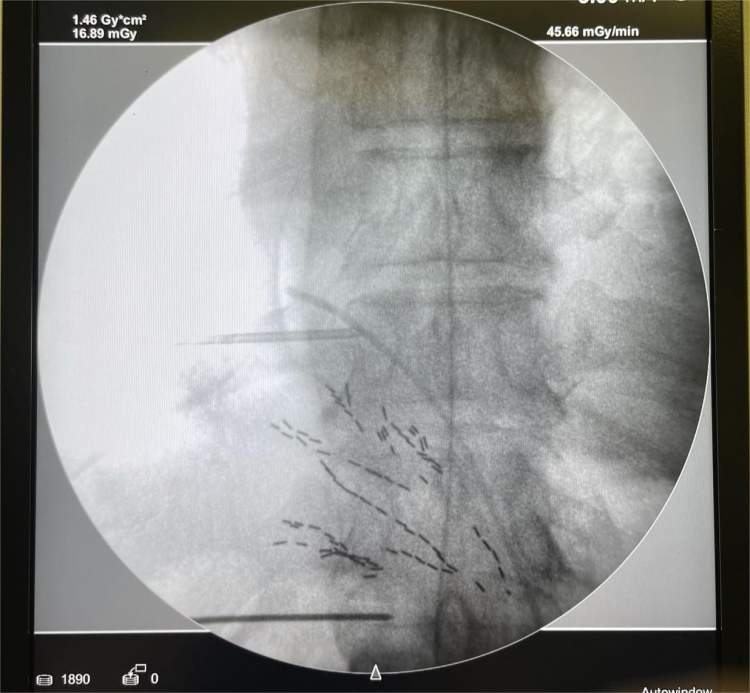

入院后,用2天时间为老陆做好了术前评估和准备,第3天进手术室在全身麻醉下,安全地完成了镇痛泵植入手术。

手术后,医生们定时评估疼痛程度,用遥控器调整镇痛泵内的药物剂量。老陆原来每天得吃500mg强效镇痛药,现在每天只需要1.7mg,因为镇痛泵导管将药物直接运送到了蛛网膜下腔,比吃药、输液,更直接、高效。